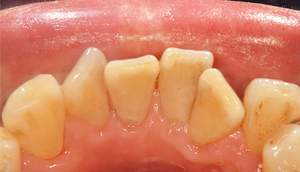

歯石除去

治療前

治療後

| 年齢 | 43歳・男性 |

| 主訴 | 歯石をとりたい |

| 治療内容 | 歯石除去 |

| 治療期間 | 30分 |

| 費用 | 約2,000円 |

| リスク・副作用 | ・歯ぐきの炎症が強いと歯石を取る際に出血することがあります ・処置後に歯がしみることがあります ・歯と歯の間に隙間ができるので、息が漏れ発音しにくいと感じることがあります ・歯ぐきの炎症が軽減すると歯ぐきが引き締まり、歯が長く見えることがあります |